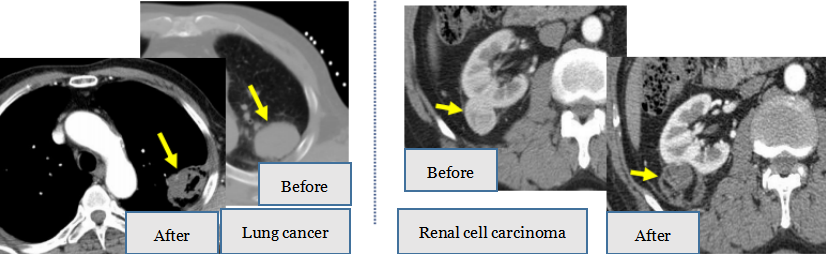

4. Solid Tumor Microwave Ablation